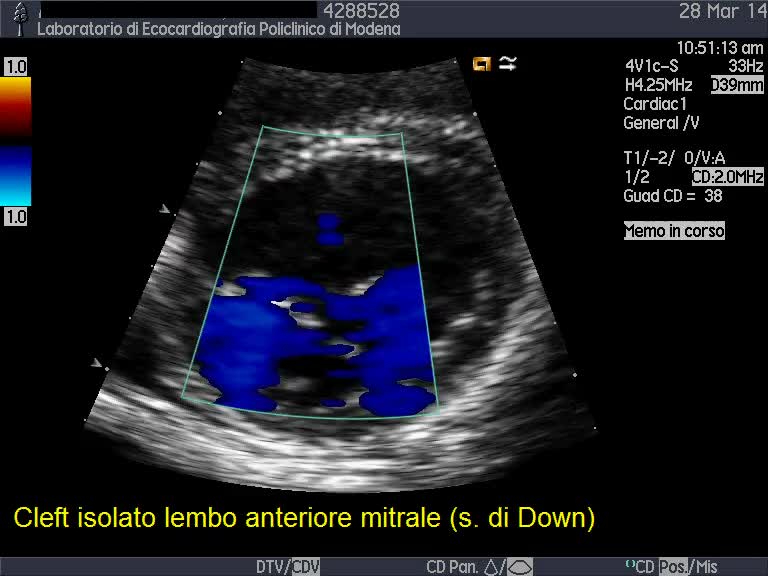

Cleft del lembo anteriore mitralico

Autore:

Andrea Barbieri